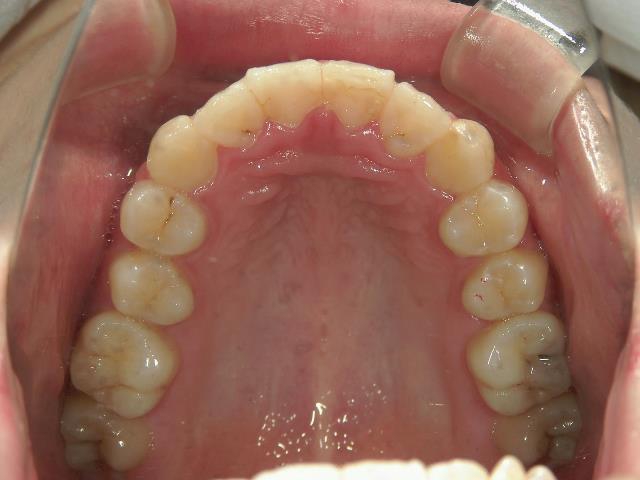

矯正歯科 治療前

矯正_灰色.pngno.6_8296_治療前_上.jpg矯正_灰色.png

矯正_灰色.pngno.6_8296_治療後_上.jpg矯正_灰色.png